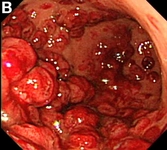

Sezaryen, doğum sırasında annenin karın bölgesine yapılan cerrahi bir müdahaledir. Bu yöntem, çeşitli tıbbi nedenlerle tercih edilebilir ve doğum sürecinde bazı riskleri beraberinde getirebilir. Sezaryen sonrasında karşılaşılabilecek en önemli komplikasyonlardan biri kanamadır. Bu makalede, sezaryen sonrası kanama belirtileri, nedenleri ve tedavi yöntemleri ele alınacaktır. Sezaryen Sonrası Kanama Nedir?Sezaryen sonrası kanama, doğumdan sonra kadının rahminden veya cerrahi kesiden kanama olması durumudur. Normal doğumda olduğu gibi, sezaryen sonrasında da kanama meydana gelebilir, ancak cerrahi müdahale nedeniyle riskler artar. Bu kanama, doğumdan sonraki ilk 24 saat içinde veya daha sonra ortaya çıkabilir. Sezaryen Sonrası Kanamanın BelirtileriSezaryen sonrası kanamanın belirtileri, şunları içerebilir:

Bu belirtilerden herhangi birinin ortaya çıkması durumunda, derhal bir sağlık uzmanına başvurulması önerilir. Sezaryen Sonrası Kanamanın NedenleriSezaryen sonrası kanamanın birkaç olası nedeni bulunmaktadır: